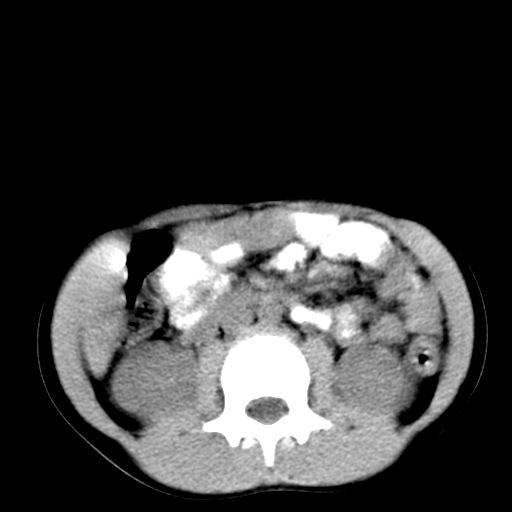

腹部好象未见异常。

腹部ct平扫未见明确异常

腹部ct平扫不能提示哪里有病变。